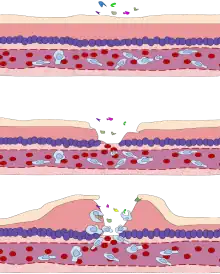

Les molécules médiatrices modifient également les vaisseaux sanguins pour permettre la migration des leucocytes, principalement des neutrophiles et des macrophages, hors des vaisseaux sanguins (extravasation) et dans les tissus. Dans des conditions normales, l'endothélium ne permet pas la sortie des protéines et l'échange se fait par pinocytose. Au cours de l'inflammation, les bases morphologiques de l'endothélium sont altérées par l'action de médiateurs chimiques, produisant une altération des jonctions cellulaires et des charges négatives de la membrane basale. Généralement, cet effet se produit dans les veinules, mais s'il est très intense, il atteint les capillaires et une extravasation se produit en raison de la rupture.

Parallèlement, les cellules endothéliales activées expriment des molécules d'adhésion (nécessaires à la diapédèse). De son côté, la diminution de la vitesse (stase) permet aux leucocytes de se marginaliser le long de l'endothélium, un processus essentiel à leur recrutement dans les tissus.

Le vaisseau devenant plus perméable, l’eau du plasma sanguin s'épanche par osmose vers les tissus.

Œdème inflammatoire

La perméabilité accrue des vaisseaux sanguins entraîne une exsudation (fuite) de liquide dans les tissus. La fuite de liquide provoque une augmentation de la viscosité du sang, ce qui augmente la concentration des globules rouges (congestion veineuse).

L’œdème inflammatoire (tumor) est donc la conséquence du passage du plasma (plus précisément d'un exsudat) dans la zone lésée. Il se traduit par un gonflement du tissu touché, et comprime les nerfs alentour, provoquant la sensation douloureuse et les démangeaisons (dolor). Certains des médiateurs libérés comme la bradykinine augmentent la sensibilité à la douleur (hyperalgésie). La perte de fonction (functio laesa) est probablement le résultat d'un réflexe neurologique en réponse à la douleur.

Une partie du liquide tissulaire exsudé sera également acheminée par les vaisseaux lymphatiques vers les ganglions lymphatiques régionaux. Dans des conditions normales, le système lymphatique filtre et contrôle les petites quantités de liquide extravasculaire qui ont été perdues par les capillaires. Au cours de l'inflammation, la quantité de liquide extracellulaire augmente, et le système lymphatique participe à l'élimination de l'œdème. De plus, dans ce cas, une plus grande quantité de leucocytes, de débris cellulaires et de microbes passe dans la lymphe, pour lancer la phase de reconnaissance et d'attaque du système immunitaire adaptatif. Comme pour les vaisseaux sanguins, les lymphatiques prolifèrent également dans les processus inflammatoires, pour répondre à la demande accrue. Les vaisseaux lymphatiques peuvent devenir secondairement enflammés (lymphangite) ou les ganglions lymphatiques peuvent devenir enflés (lymphadénite), en raison d'une hyperplasie des follicules lymphoïdes et d'un nombre accru de lymphocytes et de macrophages.

Diapédèse leucocytaire

Les molécules d’adhésion (CAM, intégrines, sélectines) libérées par les cellules endothéliales sont un signal pour les leucocytes présents dans les vaisseaux sanguins, qui dans la région inflammatoire ont tendance à quitter le milieu du courant pour s’accoler à la paroi de l’endothélium du vaisseau, par « margination », favorisée par le ralentissement du flux sanguin.

La diapédèse leucocytaire est le phénomène permettant le passage des leucocytes de la circulation sanguine jusqu'au foyer de l'inflammation. La traversée de l'endothélium par les leucocytes ou diapédèse intervient dans un segment particulier du système circulatoire : les veinules post-capillaires. On peut distinguer différentes étapes :

Après la migration des leucocytes hors des vaisseaux sanguins (extravasation), les cellules inflammatoires, dont les leucocytes, se dirigent ensuite de façon unidirectionnelle par chimiotaxie, le long d'un gradient créé par les cellules locales, pour atteindre le site de la lésion.